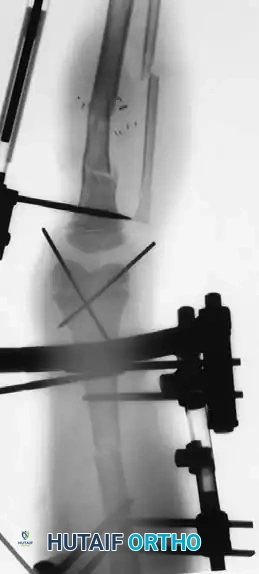

5. Fixation:

* For vertical fracture components, insert transverse guide pins.

* In older children and adolescents nearing skeletal maturity, utilize 4.0mm or 4.5mm partially threaded cancellous bone screws to achieve interfragmentary compression.

* In younger children with significant remaining growth potential, utilize smooth Kirschner wires (K-wires) placed transversely or horizontally to minimize the risk of physeal arrest.

Placement of transverse fixation pins.

Final construct utilizing cancellous screws for rigid fixation.

* Confirm joint congruity visually and via fluoroscopy.

Fluoroscopic confirmation of anatomic reduction prior to definitive fixation.